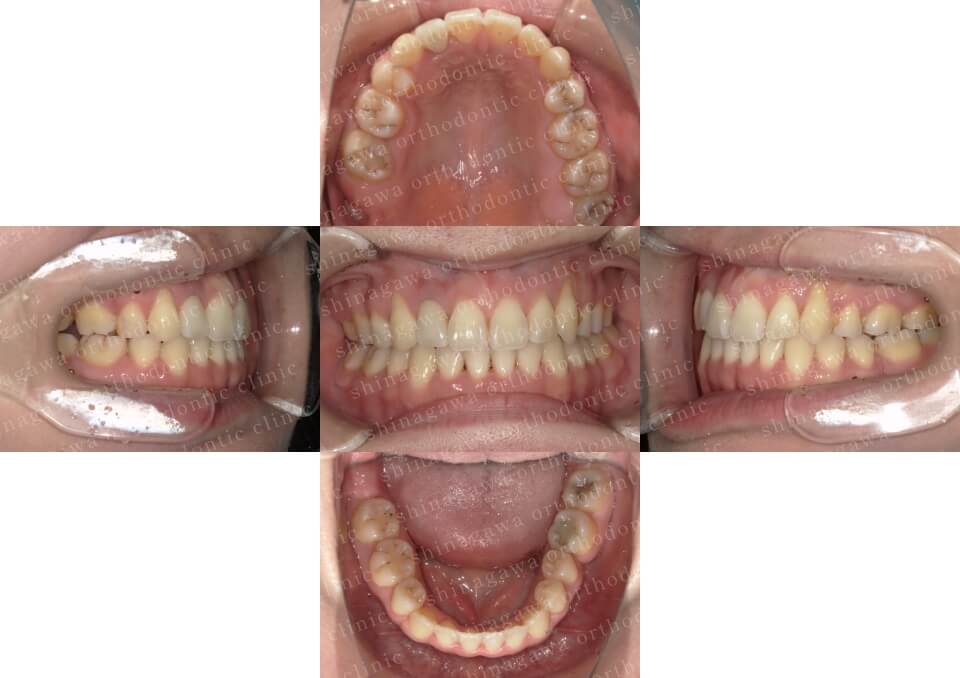

症例2

叢生、正中不一致

| 年齢 | 17 歳 |

|---|---|

| 性別 | 女性 |

| 住所 | 神奈川県横浜市 |

| 主訴 | ガタガタしている, 上下真ん中ずれ |

| 不正咬合の種類(診断) | 叢生, 正中不一致 |

| 装置 | (マウスピース型矯正装置)アライナー |

| 抜歯/非抜歯 | UR4, UL4, LR4, LL4 |

| 期間 | 18M |

| 費用 | 990,000 円 |

| リスク・副作用 | 矯正治療による歯の移動に伴う痛み, 虫歯, 歯肉退縮, 歯根吸収 |